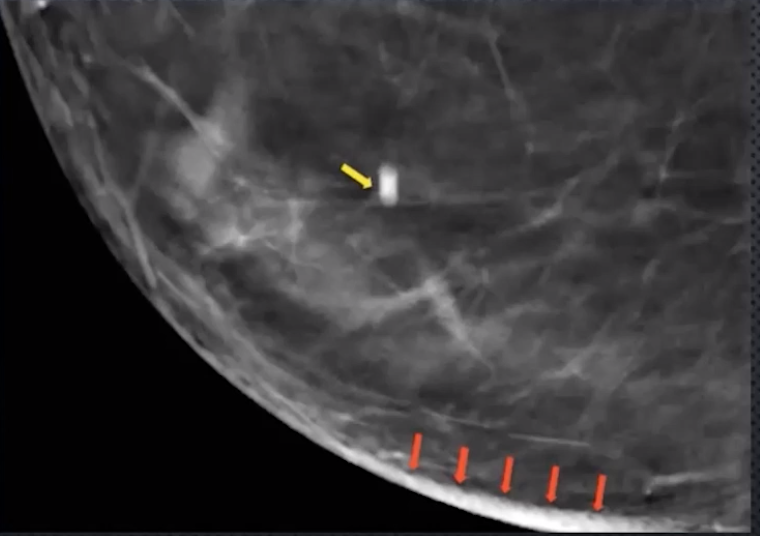

Blurring/Ripple Artifact

• Caused by limited # of acquired projections

• Occurs perpendicular to XR tube sweep direction

• Look for falsely thickened appearance of skin

• Coarse calcs and biopsy clips will have elongated slinky appearance

• Fix via post image processing